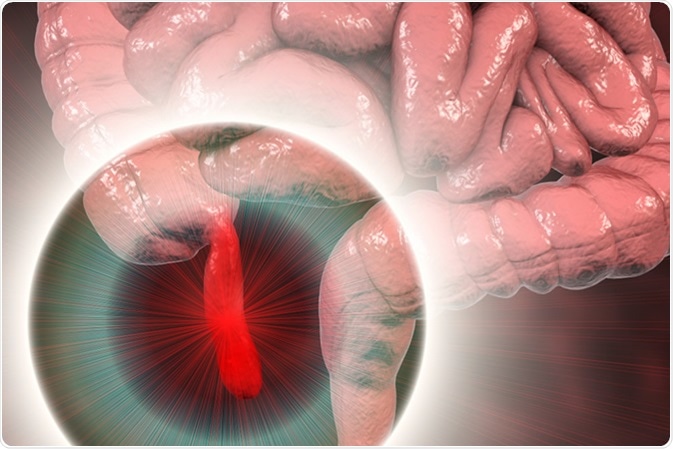

Appendicitis

Appendicitis refers to the inflammation of the appendix, a small and thin pouch connected to the colon. It can become inflamed and lead to severe pain. In severe cases, an inflamed appendix may rupture, leading to peritonitis, a serious infection of the inner lining of the abdomen. The most common symptom of appendicitis is pain that begins near the umbilical area and moves down into the right side of the lower abdomen. It gets worse in a matter of hours, but twinges of sharp pain even before that, when moving around or taking deep breaths.

Acute appendicitis, 3D illustration showing inflammed appendix on the cecum. Image Credit: Kateryna Kon / Shutterstock